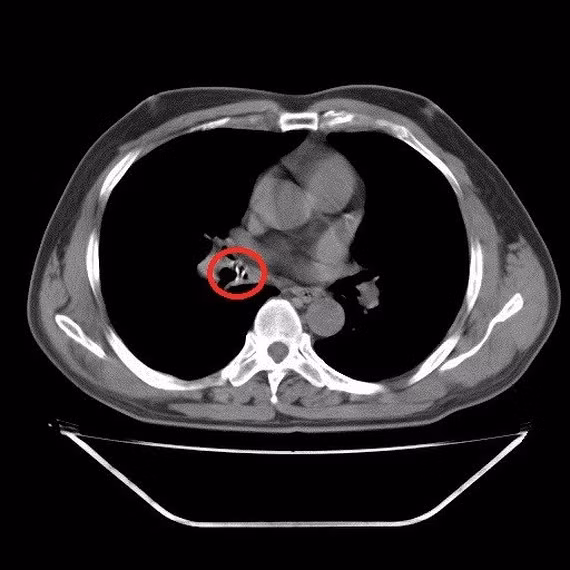

| Dị vật ở lòng phế quản trung gian phổi phải qua hình ảnh chụp cắt lớp vi tính |

Tại Khoa Nội tổng hợp, bệnh nhân Đ. được các bác sĩ cho làm các xét nghiệm cần thiết nhưng không phát hiện ra vấn đề gì. Lúc này các bác sĩ đã hỏi tiền sử của bệnh nhân trong thời gian qua thì nghi ngờ bệnh nhân bị mắc dị vật, đồng thời tiến hành chụp CT lồng ngực, qua đó phát hiện ở lòng phế quản trung gian phổi phải có dị vật.